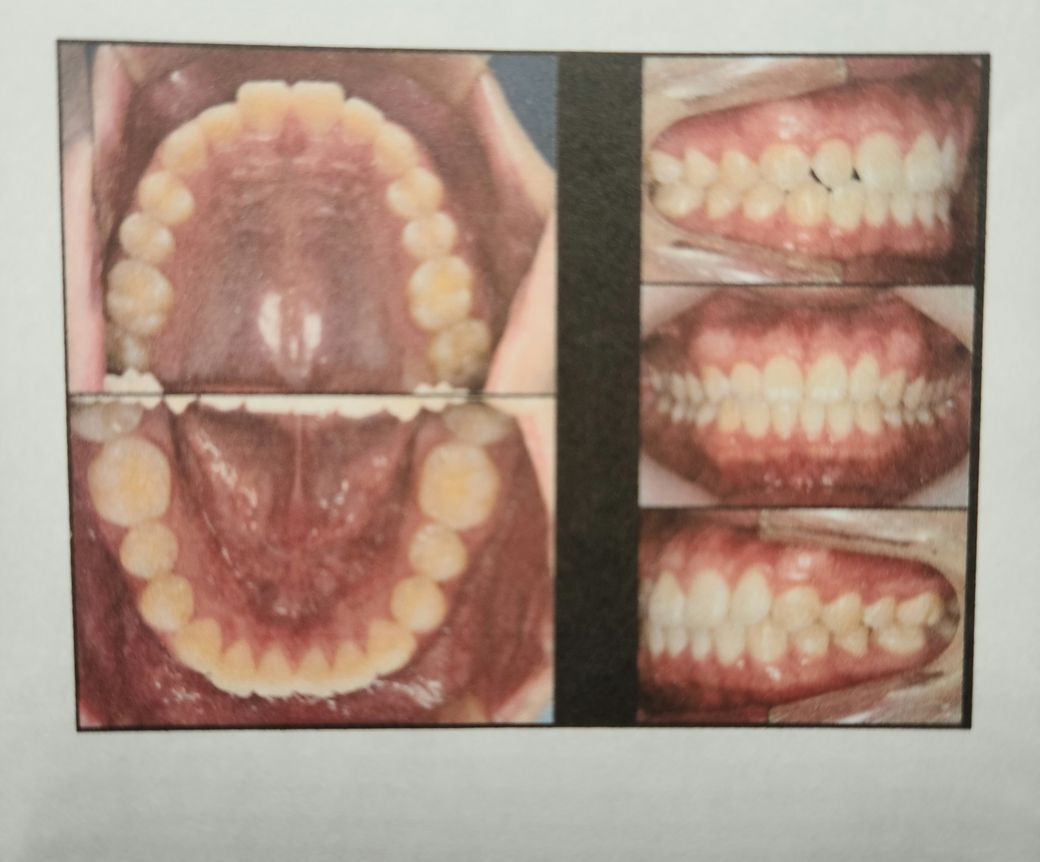

(치과자료 첨부) 반대교합,주걱턱 검사 및 돌출입 교정상담

(스케일링, 주걱턱검사, 하악긴턱 및 돌출입 교정때문에 방문했으나 치근 및 전체적인 치아각도 때문에 전체교정 추천 안 하셨음)

A치과) 상악에 비해 하악이 긴편이나 정상범위라고 볼수 있어 주걱턱은 아니라고 봅니다. 그래서 수술적 치료는 필요치 않아 보입니다. 치아상태는 전치부 총생 및 전방경사가 있고 상악 우측절치 반대교합이 있다 장기적으로는 좋지못하다. 앞니 부분교정 또는 인비절추천

대부분의 경미한 부정교합은 사람마다 있습니다. 치축 경사나 여러가지 상황을 보았을 때 정상범주이며 일부 양쪽 턱관절이 비대칭으로 발생한 턱관절 틀어짐으로 보여집니다. 이 역시 정상범주이며 예민하신 분이 아니라면 살아가는데 크게 불편감이 없어 보입니다. 인비절라인을 하더라도 크게 개선되지 않을 수 있어 보이며 신중하게 하셔야 할 것으로 보입니다.